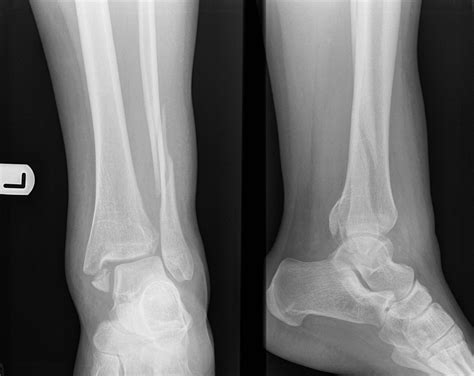

Diagnosing a Fracture Weber C involves a thorough clinical examination and imaging studies. The diagnostic process typically includes:

• Clinical Examination: Assessing the patient's pain, swelling, and range of motion. Checking for tenderness and deformity around the ankle joint.

• Imaging Studies: X-rays are the primary imaging modality used to visualize the fracture. Additional imaging, such as CT scans or MRIs, may be required to assess the extent of the injury and plan treatment.

X-rays are essential for determining the exact location and severity of the fracture. A lateral view of the ankle can help identify the level of the fibular fracture in relation to the syndesmosis. CT scans provide detailed images of the bone structure and can help in surgical planning. MRIs are useful for evaluating soft tissue injuries, such as ligament damage.